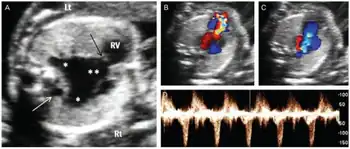

| Prenatal ultrasonographic findings of absent pulmonary valve syndrome a) Marked dilatation of main and branch pulmonary arteries b-d) color and pulsed wave Doppler ultrasound shows to-and-fro pattern of pulmonary stenosis and regurgitation | |

Absent pulmonary valve syndrome is a congenital heart defect that occurs when the flaps of the pulmonary valve do not develop.[1] It presents at birth with breathing problems and a blue appearance.[1]

There is (hypoplasia) resulting in aneurysms (dilation) of the pulmonary arteries and softening of the trachea and bronchi (tracheobronchomalacia).